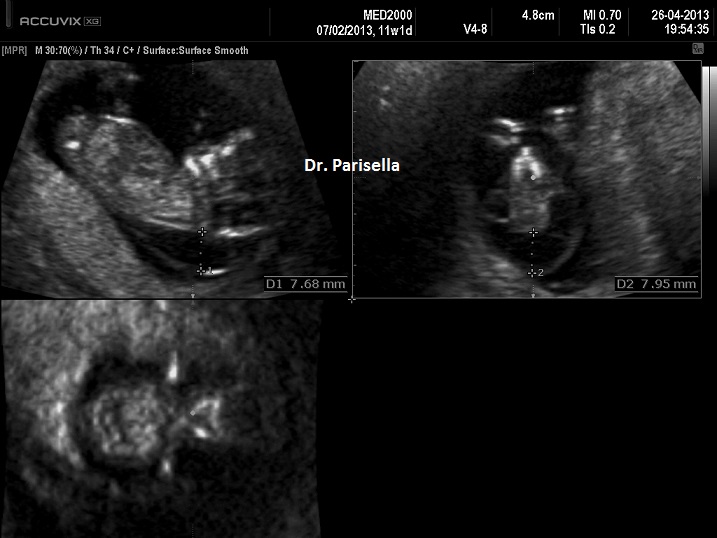

I segni principali sono la micromelia marcata, l'idrope fetale e ossificazioni ectopiche.

1. micromelia severa